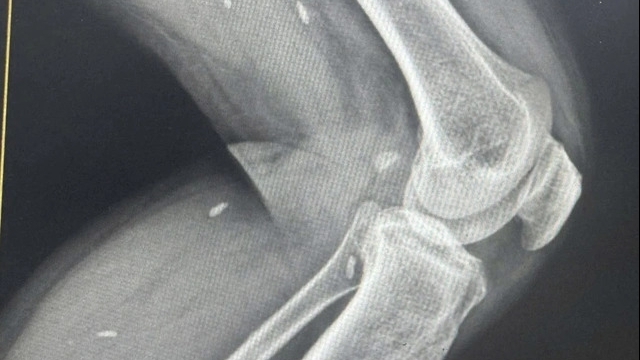

Sau hội chẩn với Khoa Hồi sức tích cực - Chống độc, ekip nội soi phế quản do bác sĩ Phan Thanh Thông thực hiện đã tiến hành nội soi cấp cứu. Dị vật là nửa quả nho xanh bít hoàn toàn phế quản gốc trái. Bằng thao tác chính xác, bác sĩ đã gắp thành công dị vật, giải phóng đường thở và cứu bệnh nhân khỏi tình trạng nguy hiểm.